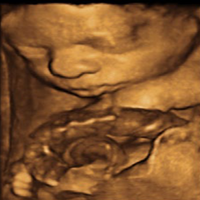

• Obstetrics